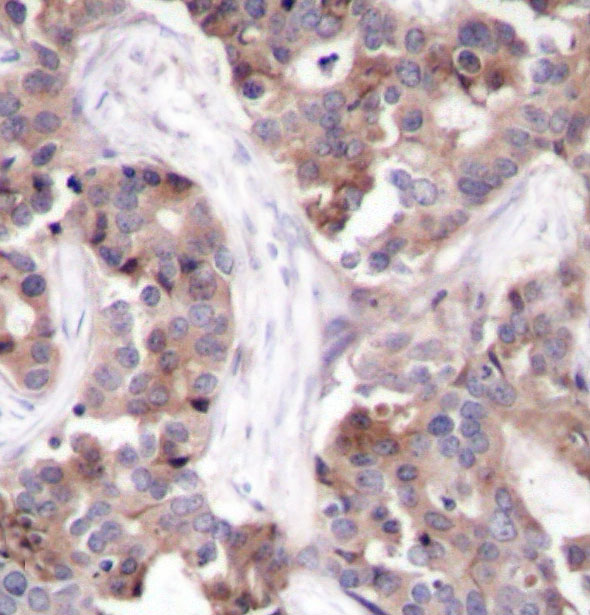

• AP0220: image 2

Immunohistochemical analysis of paraffin-embedded human breast carcinoma tissue using Phospho-STMN1-S25 antibody.